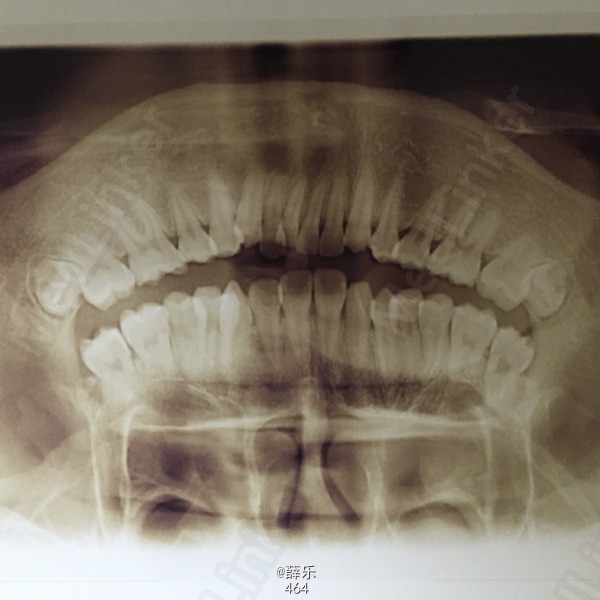

查体 辅查

恒牙列,牙列式17~27,37~47。双侧磨牙中性关系,上下牙列中度拥挤,13、23唇侧低位,38、48近中阻生,侧观呈直面型,上下前牙较直立

诊断:安氏1类错牙合伴牙列拥挤 建议:正畸治疗 处理:1.取研究模型 2.血液检查 3.全景片+侧位片+面像检查 4.约会诊